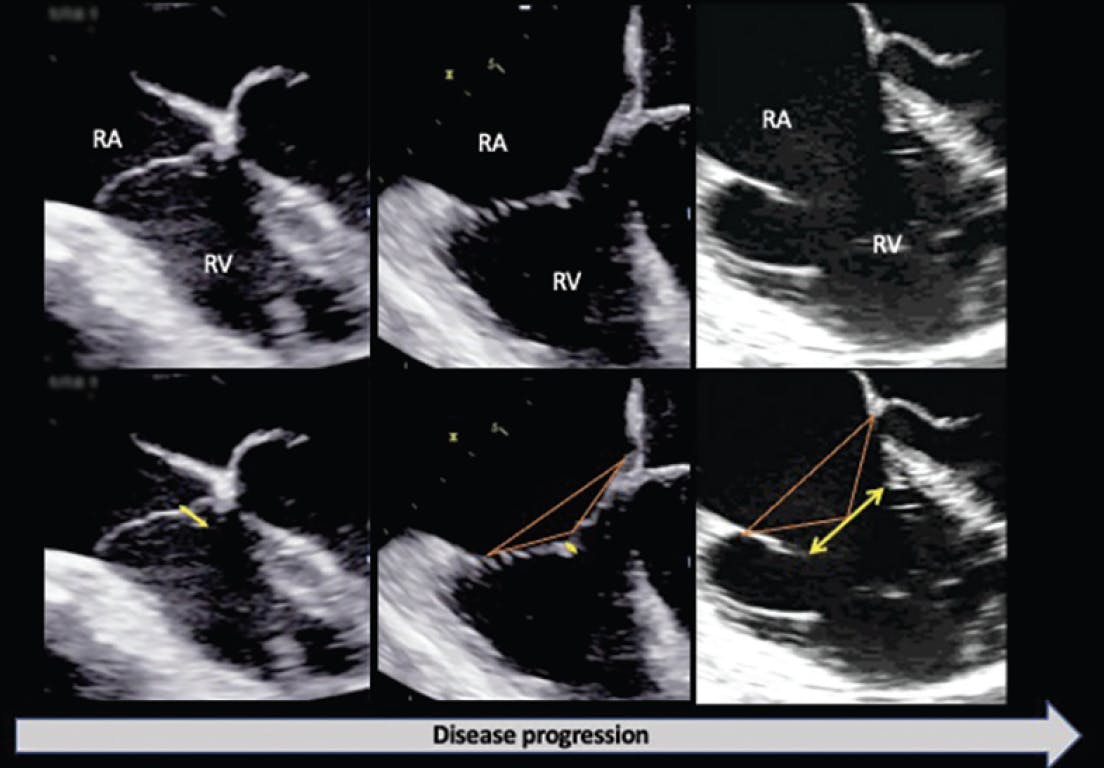

Etiology determines the lesions and the resulting anatomy of the valve. Therefore, rheumatic disease typically leads to more tethered and restricted leaflets that frequently require replacement, while degenerative disease is usually amenable to be repaired. For functional TR, the stage of disease will also determine the repairability and the technique/device of choice. Early stage functional TR typically shows mild annular dilatation, with atrial dilatation or mild right ventricular dilatation and small coaptation gaps of leaflets that can be easily repaired. On the other hand, advanced stages of functional TR show large gaps of coaptation, with advanced right atrial and ventricular remodeling and tethered leaflets that require replacement or combined repair techniques (Table 1 and Figure 1).22,23

Figure 1. Progression from normal to abnormal TV geometry in functional TR. Yellow line/arrow indicates leaflet coaptation line or gap. Red lines encircle the tenting area between the annular plane and the point of coaptation of the tip of the leaflets, indicative of local remodeling and leaflet tethering.